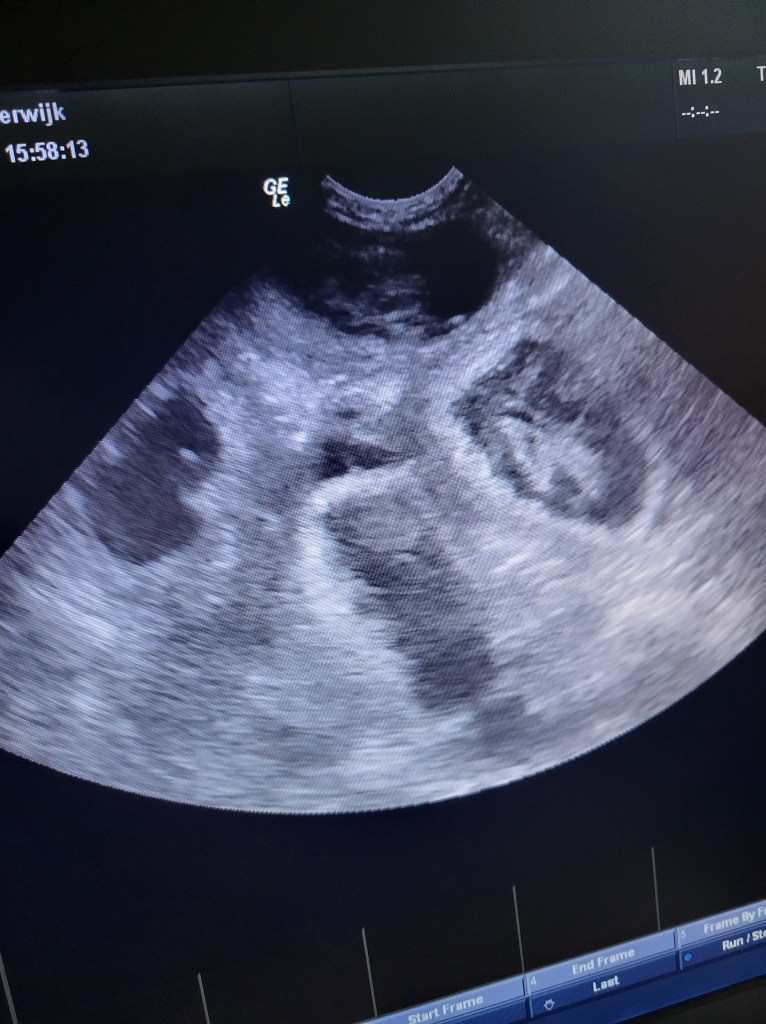

Roef is zwanger.